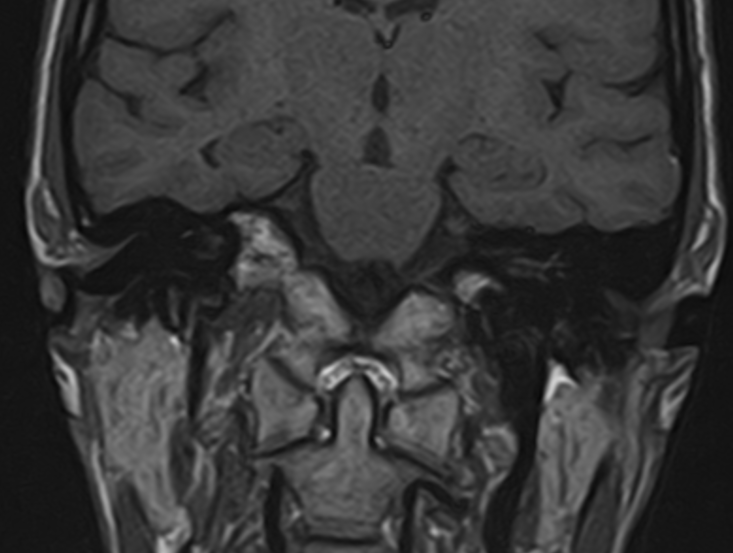

Внутреннее ухо – важная часть слуховой и вестибулярной систем тела человека, находящаяся в толще пирамиды височной кости.

Внутреннее ухо содержит слуховой орган (улитку) и орган равновесия (преддверие и полукружные каналы), патологические изменения которых в свою очередь приводят к развитию нейросенсорной тугоухости и вестибулярных нарушений.

При подозрении на опухоль преддверно-улиткового нерва, образованиях лабиринта, воспалительный процесс МРТ внутреннего уха выполняется с внутривенным введением контрастного препарата.